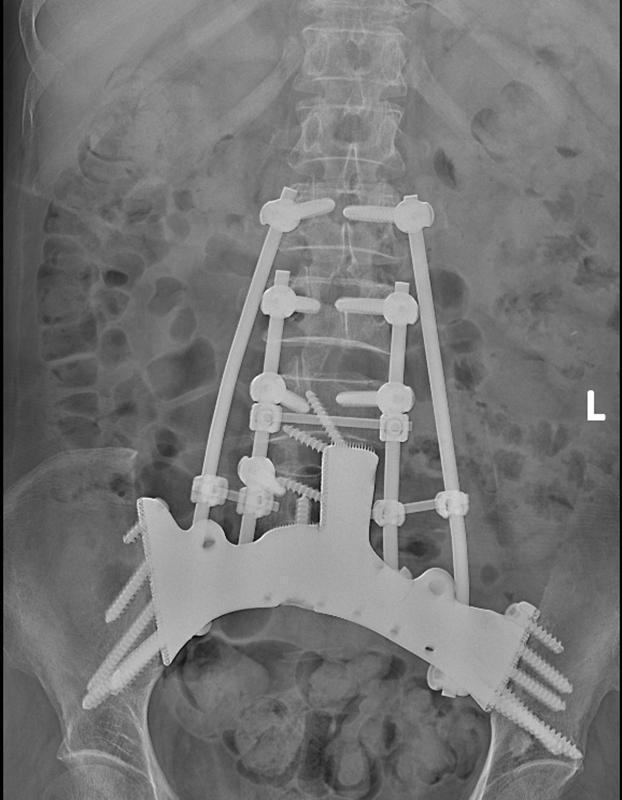

术后腰椎正位X线。

为尽最大勤恳秩序肿瘤、保留肢体功能,熊女士住院后,贵医附院骨肿瘤休养组为其进行了3D打印个体化肿瘤假体谋略,并于2024年12月收效扩充“全骶骨+半骨盆+L5椎体矢状位切除+3D打印肿瘤假体置换”手术,这亦然贵州首例“半骶骨+半骨盆+L5椎体一期切除鸠合3D打印肿瘤假体置换”病例。